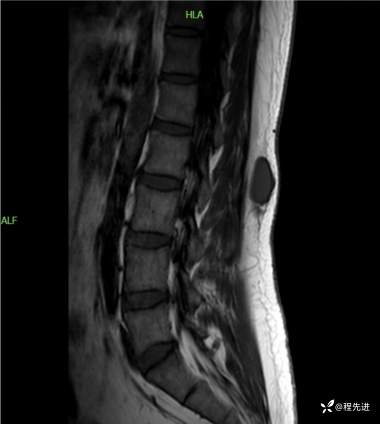

T1矢状位: